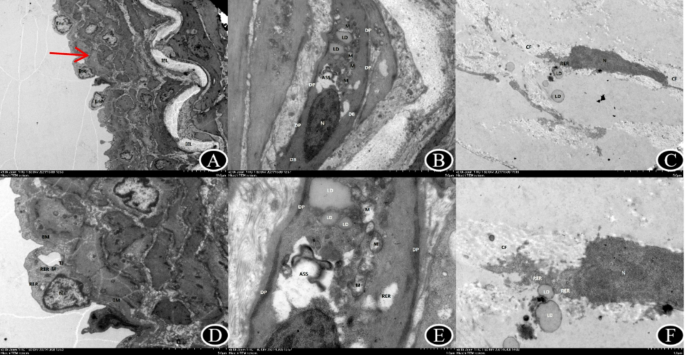

Ultrastructural characteristics (Table 4, Fig. 1)

Typical picture of TEM results of internal carotid artery occlusion (D-F is local magnification of A-C). A (X1000 times) Internal elastic lamina tear, “sandwich-like” changes, migration of a few smooth muscle cells to the intimal layer, swelling of endothelial cells with irregular nuclei and heterochromatin edge setting; abundant mitochondria showing swelling, light matrix, reduced or disappeared cristae; and dilation of rough endoplasmic reticulum. B (X3000 times) shows abundant smooth muscle cells with intact cell membranes, fewer organelles, elongated spindle nuclei, clear nuclear membranes, heterochromatin edge setting, and a small number of dense patches and dense bodies evenly distributed. C (X3000 times) reveals necrotic fibroblasts with disintegrated and free organelles, intact nuclei, and abundant collagen filaments surrounding the cells. IEL: Internal elastic lamina; Enc: endothelial cells; N: nucleus; M: mitochondria: RER: rough endoplasmic reticulum; SMC:smooth muscle cell; DP:dense patches; DB: dense body;Fb:Fibroblasts; CF: collagen filament.

Intima Vascular endothelial cells (Enc) exhibit varying degrees of edema, necrosis, and shedding in MMD. The internal elastic lamina (IEL) shows waviness, visible thinning, and rupture. Smooth muscle cells (SMC) abundantly were observed in the intimal layer. Irregular nuclear morphology with a heterochromatin border is noted, along with varying numbers of mitochondria and dilated endoplasmic reticulum.

Patients with middle cerebral artery occlusion exhibit cortical vascular endothelial cells and organelle edema, along with folding of the IEL, reminiscent of a “sandwich-like” alteration, smooth muscle cells are visible in the interstitium. Irregularities are observed in the nuclear morphology and heterochromatin borders of endothelial cells. Additionally, there are indications of mitochondria swelling and dilated endoplasmic reticulum.

Media In MMD, abundant smooth muscle cells were visible on the surface of the artery. The majority of nuclei displayed an elongated spindle shape, while the density of both dense patches (DP) and dense bodies (DB) within plaques varies. Patients with middle cerebral artery occlusion showed an abundance of smooth muscle cells with a diffuse arrangement. The nuclei were oval, containing abundant mitochondria, with a reduced density of dense bodies and dense patches.

Adventitia In MMD, there is notable fibroblast disintegration, scattered organelles, and abundant collagen fibers (CF) surrounding the cells. Patients with middle cerebral artery occlusion displayed fibroblasts edema, disintegration, organelle dissolution, and disappearance on the brain’s surface, along with abundant collagen fibers surrounding the cells.